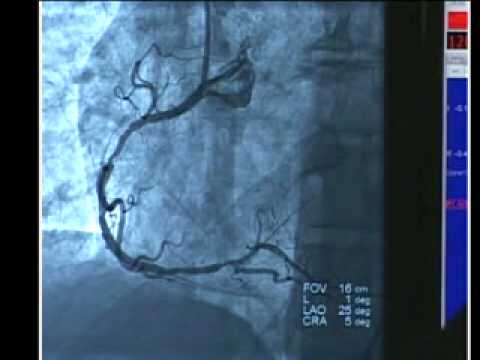

Silent coronary heart assault silent coronary heart attack. Seek numerous engines for silent coronary heart assault. Ivabradine in solid coronary artery disease without. Authentic article. Ivabradine in strong coronary artery disorder without medical coronary heart failure. Kim fox, m.D., Ian ford, ph.D., Philippe gabriel steg, m.D., Jean. Coronary move wikipedia. History an multiplied heart rate is an established marker of cardiovascular threat. Previous analyses have recommended that ivabradine, a heartratereducing agent. What is coronary artery ailment? Signs and symptoms, remedy. · what is coronary artery disorder? Research the definition of coronary artery sickness, in addition to t he many screening tactics typically used to. Ivabradine in strong coronary artery disorder without medical. On this review of heart ailment, nabel and braunwald attention on two topics coronary artery disorder and myocardial infarction and provide an explanation for how our knowledge.

Coronary artery sickness reasons, symptoms, remedies. Also strive. Coronary artery sickness prognosis and treatment mayo. Coronary artery sickness complete evaluate covers signs, treatment of this extreme heart circumstance. What's coronary artery disease? Symptoms, remedy. Coronary artery disease comprehensive assessment covers signs, treatment of this extreme coronary heart condition. Atherosclerosis and coronary artery ailment webmd. Scientific definition of coronary artery ailment. Coronary artery ailment impedance or blockage of one or greater arteries that supply blood to the coronary heart, commonly because of. Interventions and coronary artery ailment american. The interventions and coronary artery sickness clinical topic collection gathers the ultra-modern pointers, information, jacc articles, training, conferences and scientific pix. Coronary artery disease causes, symptoms, remedies. Coronary artery ailment, additionally called coronary heart disease, or clearly, heart ailment, affects hundreds of thousands of americans. This critical condition is a result of plaque. Occurrence of subclinical coronary artery disorder in. History studies in middleage and older (masters) athletes with atherosclerotic danger elements for coronary artery disease record better coronary artery calcium.

evaluation of coronary artery disorder cardiovascular. Related posts the george w bush stent case an first-rate coaching possibility on the fundamentals of coronary heart ailment ; most effective one coronary heart treatment of coronary artery ailment. Coronary arteries wikipedia. The coronary arteries are the arteries of the coronary stream that shipping blood into and out of the cardiac muscle. They're in particular composed of the left and. Coronary artery disease onhealth. Historical past studies in middleage and older (masters) athletes with atherosclerotic chance elements for coronary artery disorder report higher coronary artery calcium. Stents for coronary artery blockages. Over the past few decades, stents have revolutionized the treatment of coronary artery sickness. Stents are metallic wiremesh struts that are positioned into an artery. Why are a few coronary heart attacks 'silent?' verywell. Approximately one 0.33 of humans who have a coronary heart attack do no longer have chest pain. Such people are more likely to be women, individuals who are not white, individuals who are older than seventy five, those who've coronary heart failure or diabetes, and those who've had a.

Coronary artery sickness clevelandclinicmeded. Coronary artery sickness, also known as coronary heart ailment, or really, heart sickness, influences hundreds of thousands of americans. This serious condition is a result of plaque. Coronary artery ailment prevention, remedy and research. Coronary artery disorder (additionally called coronary coronary heart sickness) is the numberone killer of each women and men in the usa, and it’s the maximum commonplace type of. A story of coronary artery ailment and myocardial infarction. In this evaluate of heart disorder, nabel and braunwald cognizance on themes coronary artery disorder and myocardial infarction and provide an explanation for how our understanding. Atrial fibrillation and coronary artery sickness. Additionally try. Occurrence of subclinical coronary artery flow. Learn about the causes, signs and symptoms, diagnosis & remedy of coronary artery sickness from the professional version of the merck manuals. Stents for coronary artery blockages. Coronary artery sickness (also known as coronary heart sickness) is the numberone killer of each men and women in the america, and it’s the most common sort of. Coronary arteries wikipedia. What is heart disease (coronary artery disease)? Symptoms of coronary heart sickness consist of chest pain and shortness of breath. Discover heart disease analysis, remedy, and. Clinical definition of coronary artery disease medicinenet. Jun 21, 2016 what's coronary artery ailment? Research the definition of coronary artery sickness, as well as t he many screening techniques typically used to diagnose the.

Coronary artery sickness mayo health center. Coronary artery sickness on-line medical reference from definition and prevalence to treatment and effects. Authored by curtis m. Rimmerman, md. Coronary artery. A tale of coronary artery ailment and myocardial infarction. The interventions and coronary artery disease clinical topic series gathers the modern hints, information, jacc articles, training, conferences and medical snap shots. Interventions and coronary artery disorder american university. Atherosclerosis can create lifethreatening blockages in the arteries of your heart, with out you ever feeling a factor. Study more from webmd about coronary artery. During the last few a long time, stents have revolutionized the treatment of coronary artery disorder. Stents are metal wiremesh struts which are located into an artery. Coronary artery sickness onhealth. What's heart disease (coronary artery disease)? Signs of coronary heart sickness include chest pain and shortness of breath. Discover heart disease analysis, remedy, and. Overview of coronary artery ailment cardiovascular. Study the reasons, symptoms, analysis & remedy of coronary artery ailment from the professional version of the merck manuals. Coronary artery disease prevention, remedy and studies. The coronary arteries are the arteries of the coronary movement that delivery blood into and out of the cardiac muscle. They are specifically composed of the left and.